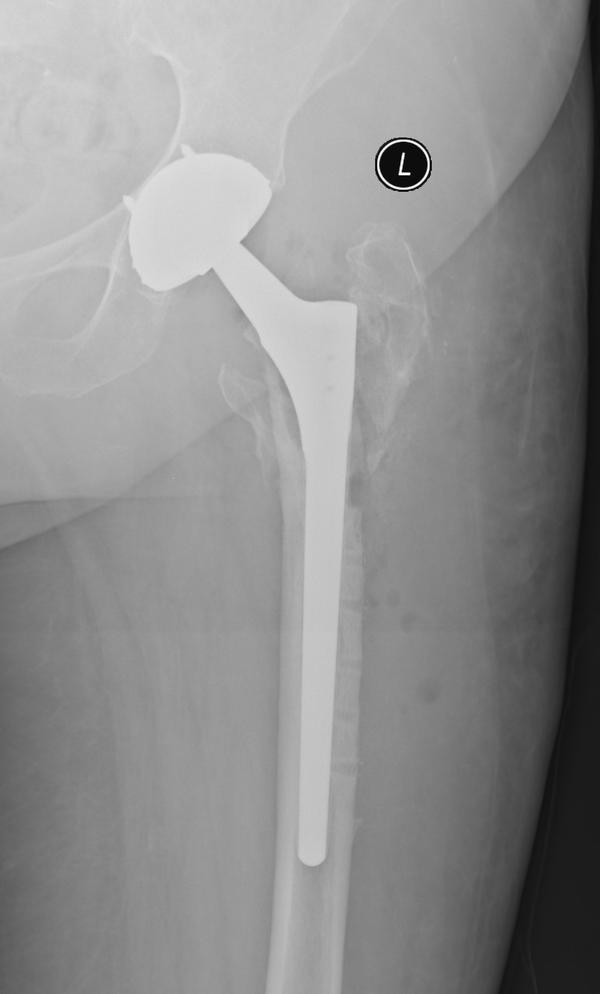

services